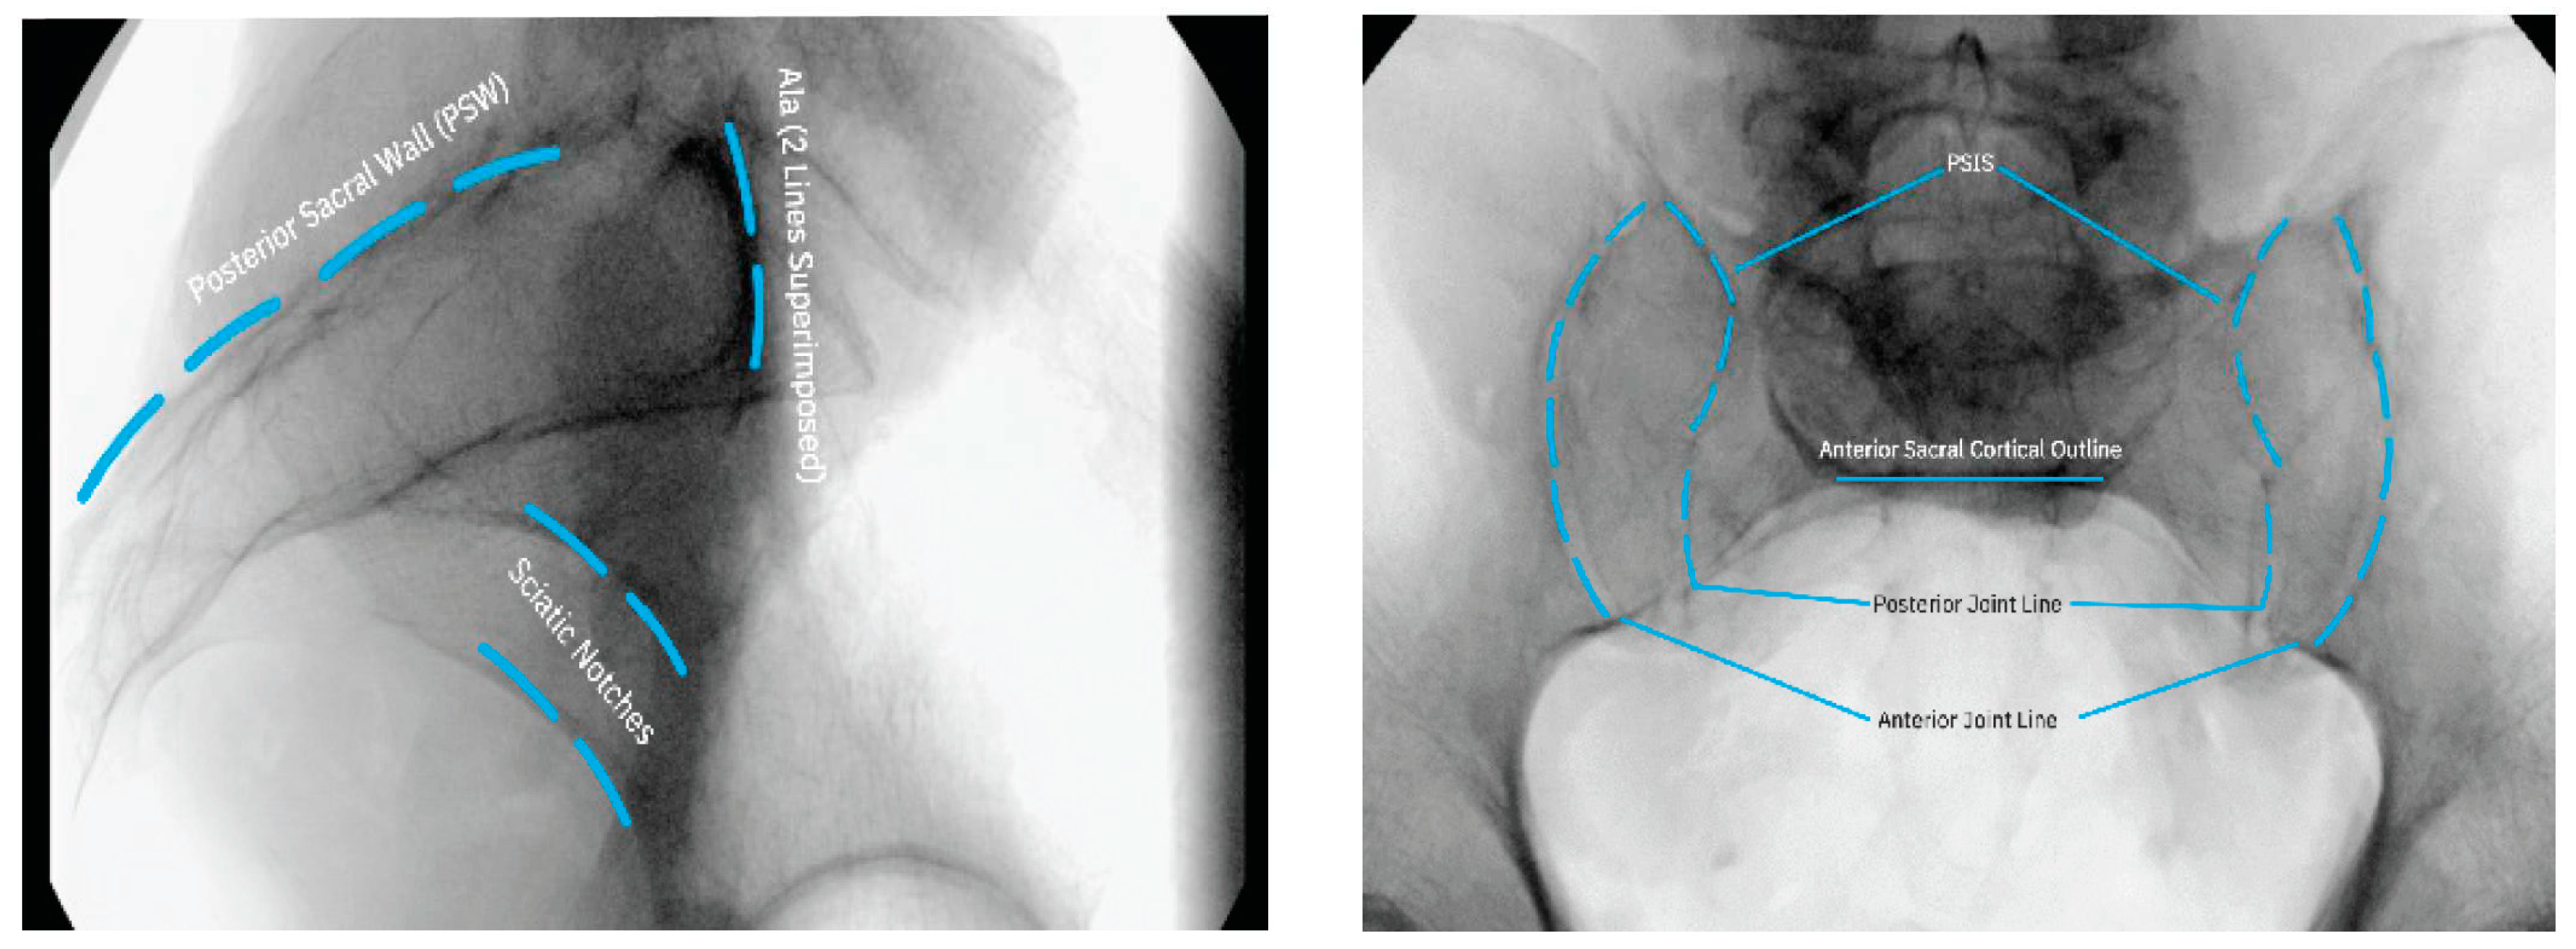

Once the patient is properly positioned, fluoroscopic imaging should be undertaken to obtain lateral, oblique, inlet, and AP/outlet views to identify the SIJ and its anatomical extent (Figure 2).

Figure 2. Intraoperative fluoroscopic imaging prior to incision indicating the location and extent of the SIJ.